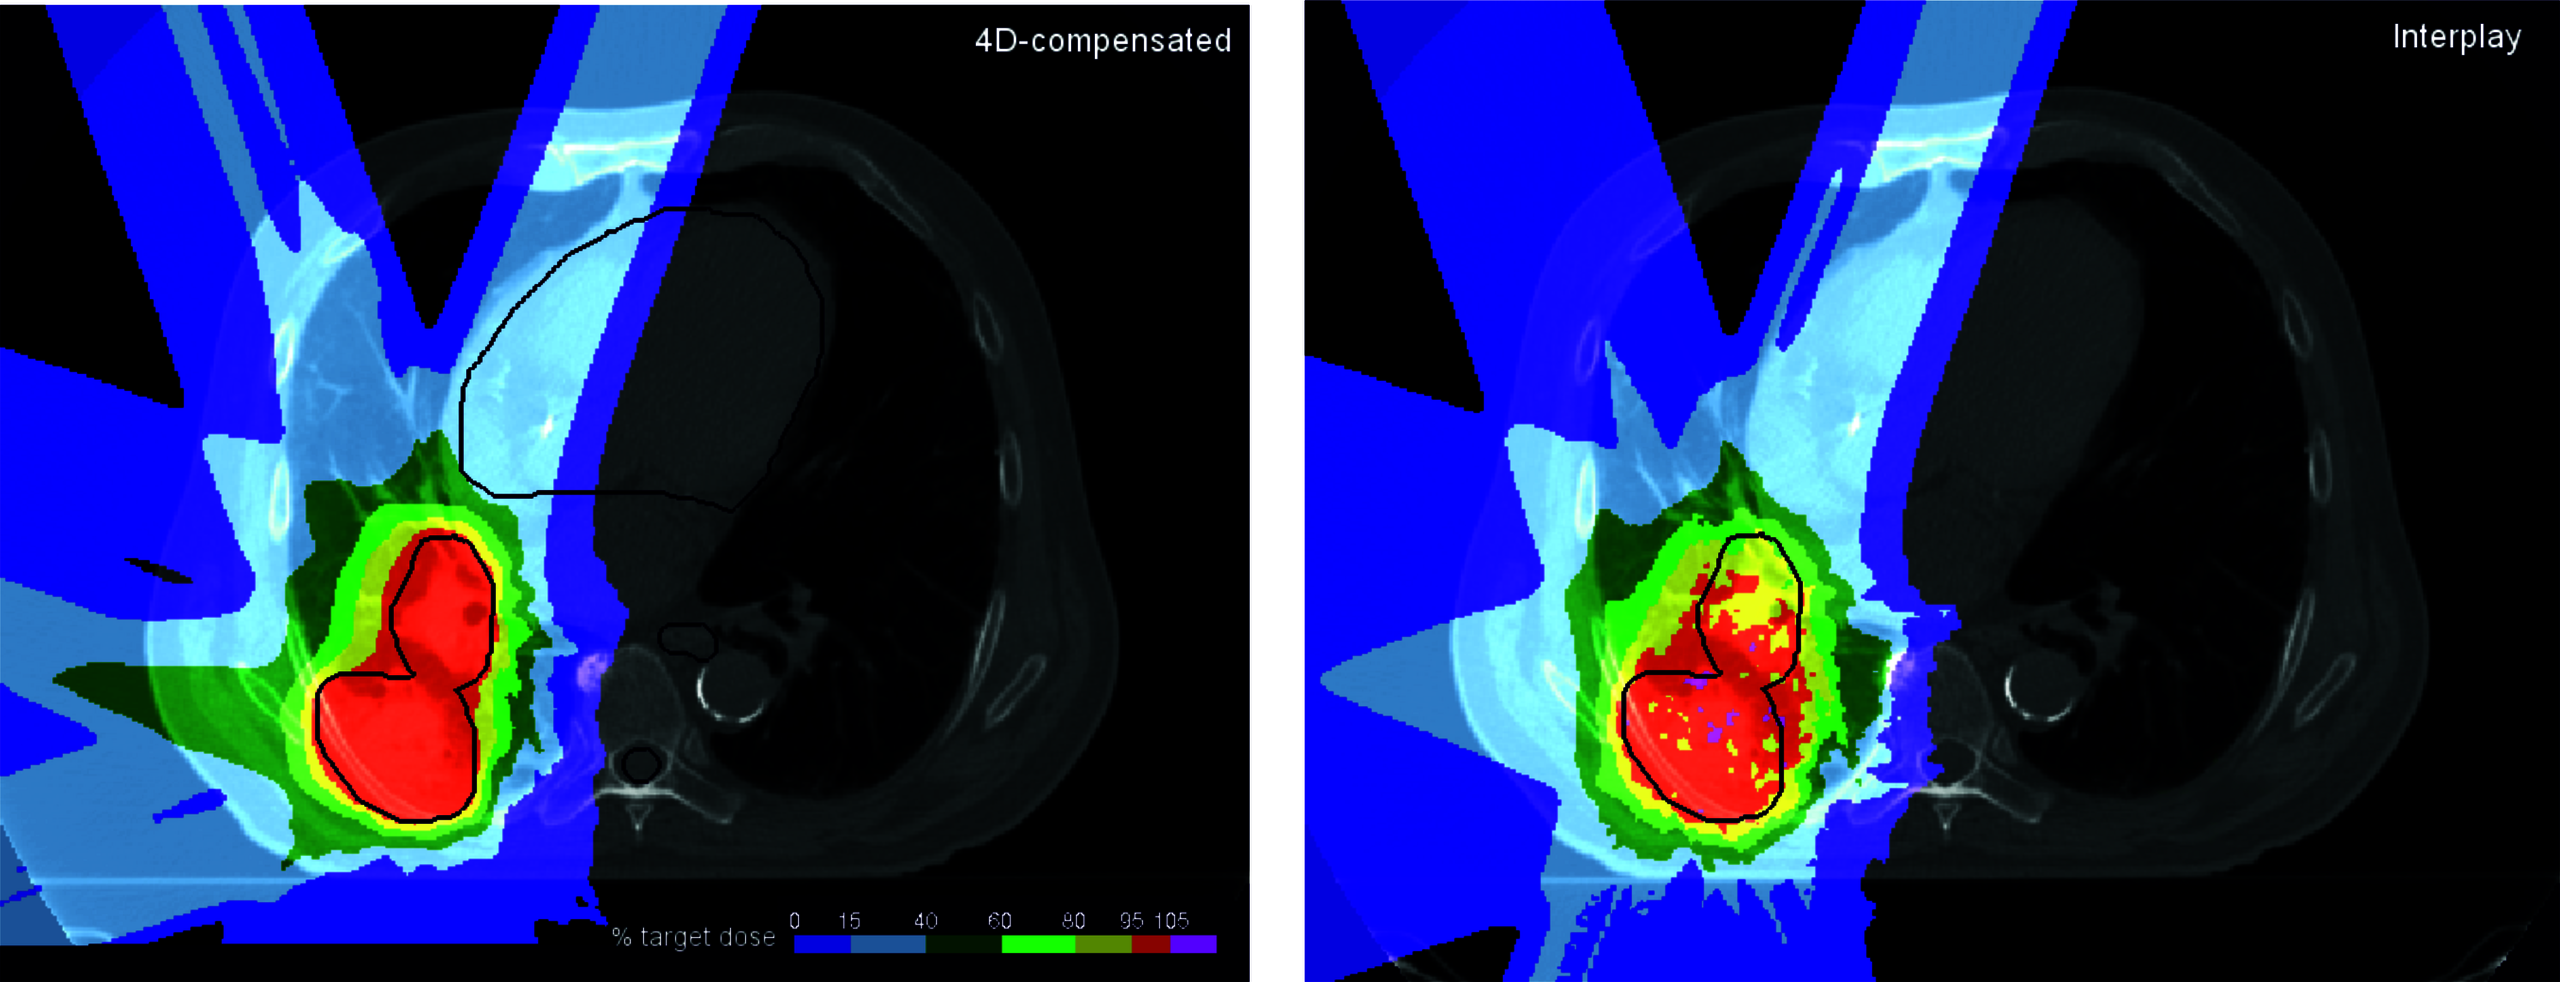

Im Vergleich zu konventioneller Röntgen-Bestrahlung ist die Behandlung bewegter Tumoren beispielsweise in der Lunge, der Leber oder den Nieren allerdings komplex. Zwei zusätzliche Faktoren spielen eine Rolle: (1) Interferenz zwischen der Tumorbewegung und der Scanbewegung des Strahls (Interplay) und (2) eine Veränderung der Strahlreichweite zum Ziel durch dessen Bewegung.

Interplay verursacht sehr variable Über- und Unterdosierungen, die es verhindern, dass Sicherheitssäume ähnlich wie in der Photonen-Bestrahlung zur Bewegungskompensation ausreichen. Die endliche Reichweite von Partikelstrahlung in Materie ist ein großer Vorteil für Ionen, erfordert aber präzises Wissen über die „radiologische Weglänge“ des Strahls bis zum Ziel. Diese Weglänge ändert sich aber mit der Bewegung vor allem in der Lunge, so dass spezielle Kompensationsstrategien unerlässlich sind.

In der Gruppe Medizinische Physik wurden effiziente Verfahren zur Bewegungskompensation entwickelt und untersucht, unter anderem Gating (unterbrochene Bestrahlung), Tracking (Strahlnachverfolgung) und 4D Optimierungsstrategien. Alle Techniken wurden implementiert und auch experimentell am medizinischen Bestrahlungsplatz der GSI (Cave M) mit verschiedenen Bewegungsplattformen und Phantomen validiert. Das Ziel dieser Forschung ist eine möglichst konforme Bestrahlung bei maximaler Schonung des normalen Gewebes zu erreichen.